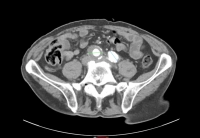

Exemplo de vídeo:

- AAA infrarrenal, diâmetro 54,2 mm

- aneurisma da artéria ilíaca comum direita, diâmetro 41,1 mm